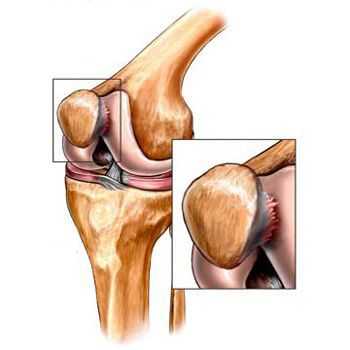

Основным методом инструментальной диагностики является рентген коленных суставов в двух проекциях, который позволяет увидеть структурные изменения бугристости [4] .

Фрагментацию с отрывом костного фрагмента лучше всего видно на боковой рентгенограмме [10] .

![Отрыв фрагмента кости [17]](/pimg3/osteoxondropatiya-bugristosti-bolshebert-21973C.jpeg)